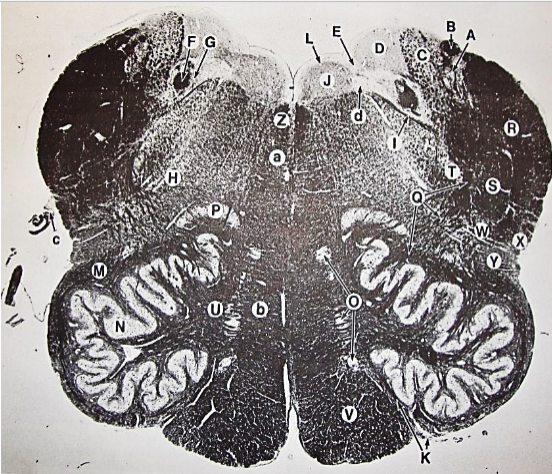

A

fasciculus gracilis

B

gracile nucleus

C

fasciculus cuneatus

D

cuneate nucleus

F

internal arcuate fibers

G

decussation of internal arcuate fibers

H

medial lemniscus

I

hypoglossal nucleus

J

dorsal motor nucleus vagus

K

solitary fasciculus

L

solitary nucleus

M

dorsal longitudinal fasciculus

N

spinal trigeminal tract

O

spinal trigeminal nucleus

P

posterior spinocerebellar tract

Q

anterior spinocerebellar tract

R

spinal lemniscus

S

lateral vestibulospinal tract

T

rubrospinal tract

U

lateral reticular nucleus

V

medial accessary olivary nucleus

W

pyramidal (corticospinal) tract

X

arcuate nucelus

Y

medial longitudinal fasciculus

Z

tectospinal tract

a

fascicles of hypoglossal nerve